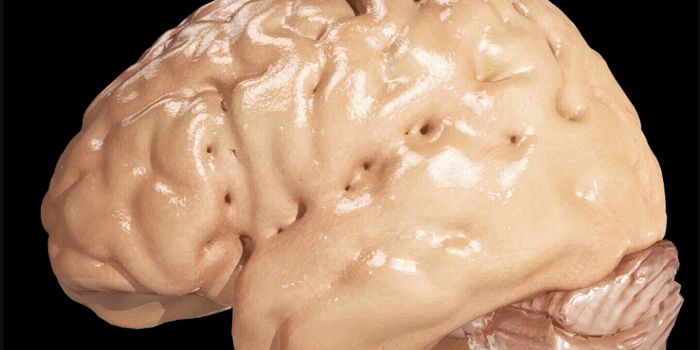

JUL 19, 2017MicrobiologyAn examination of post-mortem brains of Alzheimer's patients revealed bacteria in different levels and proportions than ...